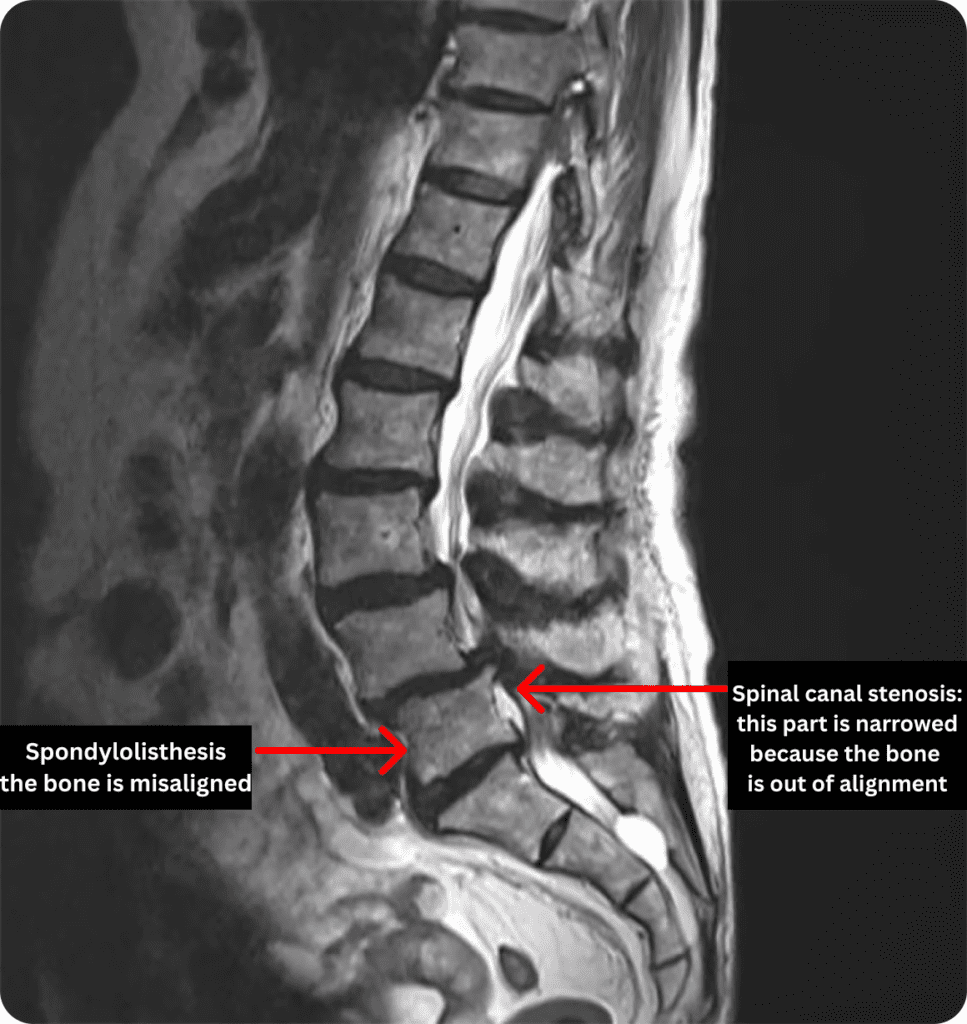

Spondylolisthesis + Spinal Canal Stenosis (example of combined conditions)

In the MRI image above, a negative chain reaction is occurring: the bone displacement (spondylolisthesis) is causing a narrowing of the nerve pathway (spinal stenosis).

So it’s not just about looking at the misalignment itself, but how it affects the nerves and surrounding inflammation. Unraveling this complex interplay is the essence of the ILC diagnosis.